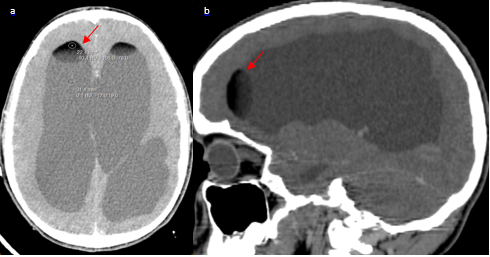

A 12-year-old male patient with a 2 months history of intermittent headaches, presented with acute onset nausea, headache, and projectile vomiting while sitting at school. After seeking medical attention, he was found to be neurologically intact on physical exam. CT scan of the head was performed and demonstrated a mixed density mass in the pineal region with central calcifications, and soft tissue components (Figure 1). Hypodense lesions were seen in the lateral ventricles, third ventricle, and quadrigeminal cistern. The lesions in the lateral ventricles demonstrated hypo attenuations as low as -93 Hounsfield Units, consistent with fat with frontal horn level (Figure 2 & Figure 3). Ventriculomegaly was also evident, due to the obstruction of the aqueduct of Sylvius.

Figure 1 Non-enhanced cerebral CT scan (a), shows a mixed heterogeneous mass extending from the pineal region anteriorly into the cistern of the velum interpositum. The mass contains a central calcification with tissue component (enhancement) on both the axial (b) and the coronal (C) post contrast CT scans.